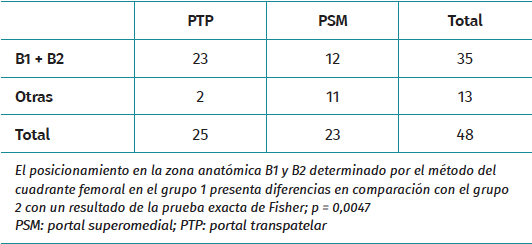

Perpendicularmente a la línea de Blumensaat y con la superficie articular anterior y posterior como límite, la superficie se divide en 4 espacios de igual longitud. Estos espacios constituyen el eje de abscisas, que se identifican de posterior a anterior con las letras A, B, C y D. El correcto posicionamiento del TF para la inserción femoral del LCA corresponde al área delimitada según este eje de coordenadas del método del cuadrante femoral con los valores B1 y B2 que se muestran en la Figura 4B. El principal resultado radiológico fue la posición del TF, que se llevó a cabo mediante dos proyecciones radiológicas un mes después de la intervención: una proyección AP y una P a 30° de flexión. La proyección AP se utilizó para medir el ángulo formado entre la superficie articular bicondilar.

Las variables continuas se presentan como media, desviación estándar o error estándar de la media. Las variables categóricas se presentan como frecuencias. La relación entre variables se analizó con tablas de contingencia para las categóricas y la inferencia se estudió con la prueba t de Student para analizar variables cuantitativas y la prueba exacta de Fisher para variables categóricas. Se utilizó la prueba t de Student para la medición angular en la proyección coronal y la prueba exacta de Fisher se usó para estudiar su posicionamiento en la proyección sagital. Shapiro-Wilk se utilizó para las variables cuantitativas que no se distribuyen normalmente. Se realizó un análisis estadístico mediante la prueba de Mann-Whitney (Tablas 1 y 2) para comparar la evaluación clínica y comprobar si existían diferencias significativas en cuanto a la pérdida de función y el dolor en los grupos de PSM y PTP. El nivel de significación se fijó en el 5% (α = 0,05). Los datos se analizaron mediante el programa SPSS 19 (SPSS Inc., Chicago, Illinois).

El PTP dio lugar a una verticalidad del TF marginalmente mayor (38,76 ± 7,04°) en comparación con el PSM (34,65 ± 6,44°; p = 0,041). Sin embargo, una parte de los pacientes de ambos grupos presentaban ángulos del túnel fuera del intervalo óptimo de 30-55°. El posicionamiento axial óptimo del TF en B1/B2 fue más frecuente con el PTP (92 frente a 52%; p = 0,0047) (Tabla 2).

Ambas técnicas mantuvieron un rango de inclinación aceptable en general, pero la mejora con PTP fue pequeña y debe interpretarse con cautela. Además, el posicionamiento axial óptimo en las zonas B1/B2 fue más frecuente con el PTP, lo que sugiere una posible ventaja en la colocación del túnel. Sin embargo, estas diferencias radiográficas no se tradujeron en beneficios clínicos significativos, ya que el dolor y los resultados funcionales a los 5 años fueron similares entre los grupos.